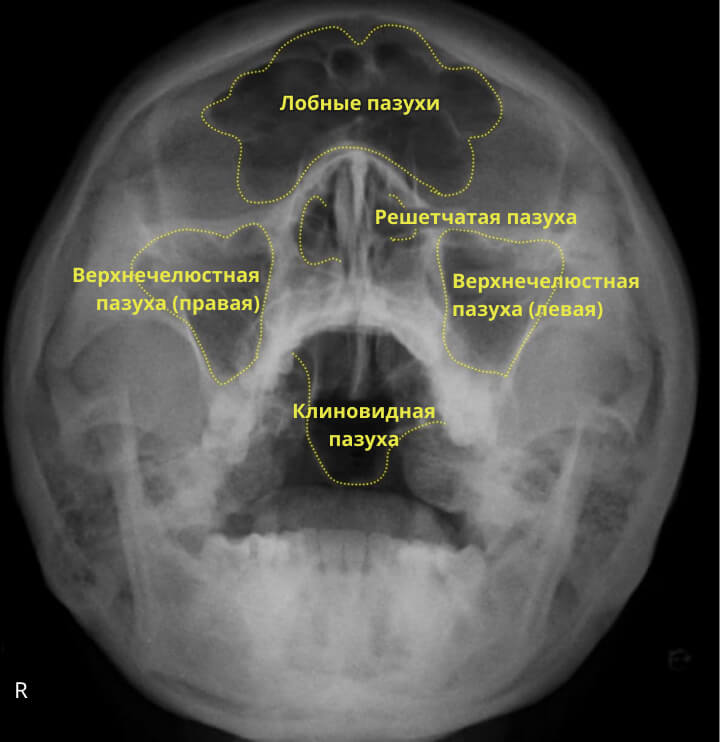

Хурц хэлбэрийн дайвар хөндийн үрэвсэл нь хамар, хамрын дайвар хөндийн үрэвслийн үед элбэг тохиолддог, ингэхдээ хамрын хөндийн дайвар салстын үрэвсэл явагддаг. Хурц хэлбэрийн хамар, хамрын дайвар хөндийн үрэвсэл үзлэг ба асуумжийн үед сайн оношлогддог. Нянгийн гаралтай халдвар эсвэл хүндрэл үүссэн сэжиг байвал рентген зураг авах аргаар оношилгоог хийдэг.

Рентгений баруун талын зургийг харахад дээд эрүүний хоёр талт хурц хэлбэрийн идээт хамрын дайвар хөндийн үрэвсэл байгааг харуулсан байна, үүгээр дайвар хөндийн хонход хэвтээ түвшинд шингэн хуримтлагдсан байгааг баталж болно. Зүүн хонх нь ойролцоогоор 1/3-ээр илүү шингэнтэй, баруун хонх нь тал хэсэг нь шингэнээр дүүрсэн байна.